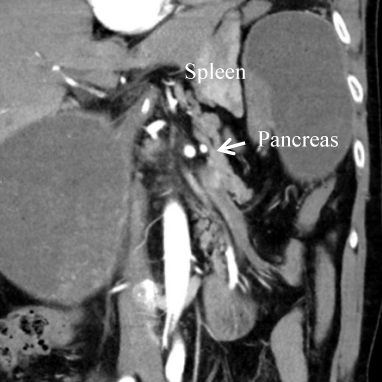

An emergency CT scan of the abdomen revealed a dislocation of the anatomical cardia to the right lower epigastrium and the gastric antrum to the left upper side (Figure 1 [Fig. 1]), spleen and tail of the pancreas were shifted medially (Figure 2 [Fig. 2]). The stomach appeared massively distended (Figure 3 [Fig. 3]). There was no free gas in the abdominal cavity and there were no direct signs of gastric gangrene.

Figure 2: CT scan: spleen and pancreas tail shifted medially